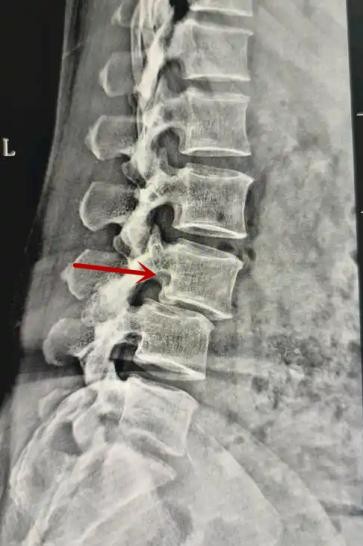

腰椎X線片作為最基礎(chǔ)的影像檢查手段,利于X線穿透人體組織后成像,以其快捷、直觀、價格低廉的特點,X線檢查主要包括腰椎正側(cè)位、雙斜位以及過伸過屈位。主要用于觀察腰椎骨骼的情況,如椎體是否有骨折、骨質(zhì)增生程度、生理曲度的變化、椎體移位的情況等。然而,X線檢查也有它的局限性,無法判斷是骨折的新舊,對于椎體內(nèi)部結(jié)構(gòu)和周圍肌肉韌帶組織(如脊髓神經(jīng)、椎間盤、韌帶等)的顯示不佳,另外X線作為有輻射檢查,孕婦及嬰幼兒謹(jǐn)慎選擇。

箭頭提示腰3椎體滑脫